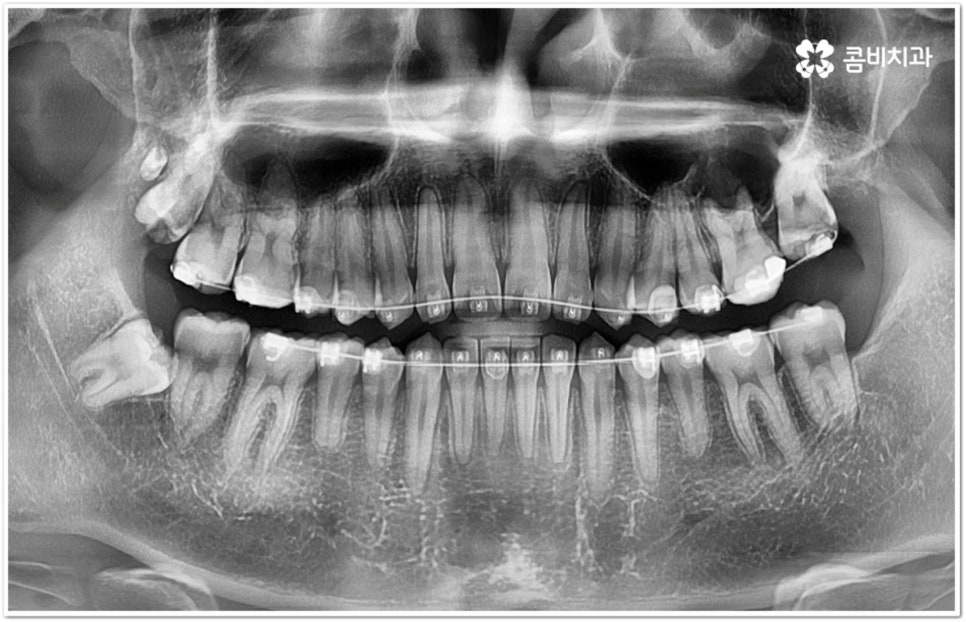

만약 똑바로 자라나고 관리가 용이하며 마주보는 대합치 역시 정상적으로 맹출되었다면 사랑니를 꼭 발치할 필요는 없을 거예요. 그러나 보통 사랑니는 사람의 치아 중에 가장 마지막에 나오는 치아라서 이미 구강 내 공간이 비좁은 상태이기 때문에 비스듬하게 자리를 잡고 일부분만 맹출이 되는 경우가 많이 있어요. 보통 머리가 앞쪽으로 기울어진 근심위로 자리잡는 케이스가 가장 많으며 그 밖에도 치아 머리가 뒤쪽으로 기울어져 있거나 혀쪽, 볼쪽으로 누운 케이스, 아예 옆으로 완전히 누운 케이스 등도 발견되고 있는데요.

잇몸에 반쯤 덮힌 채로 삐뚤게 나온 사랑니는 칫솔질을 제대로 하기 어렵고 위생 관리가 잘 되지 않아 주변 잇몸에 염증이 생기기 쉬우며 어금니까지 충치가 번질 위험이 높아지게 되어 구강 건강 관리 및 예방 차원에서 발치 처치를 해주실 필요가 있어요. 발치 난이도는 사랑니의 경사 각도와 방향 및 치아 뿌리의 길이와 개수, 사랑니 뒤쪽 턱 뼈의 각도 및 형태, 하치조 신경 또는 상악동까지의 거리 등에 따라서 달라질 수 있습니다.

이때 아래사랑니발치 의 경우 아래턱 부근을 지나가는 큰 신경인 하치조 신경을 건드리지 않고 조심스럽게 사랑니만 제거해야 하기 때문에 3D-CT 등 정밀 검진 기계를 통해 사랑니의 매복 위치, 깊이, 각도 등의 상태와 신경까지의 거리 등을 먼저 꼼꼼하게 파악한 후에 발치를 해 줄 필요가 있는데요. 만약 완전히 매복되어 있다면 사랑니 주변에 함치성 낭종이 발생할 수도 있는데 이로 인해 주변 치조골이 파괴되고 어금니 쪽으로 병변이 확산되면 결국 치아를 상실하게 되거나 턱뼈가 약해져서 작은 충격에도 부러지는 현상이 발생할 가능성도 있으므로 될 수 있는대로 치료 시기를 놓치지 않는 것이 중요한 포인트라고 할 수 있어요.

아래사랑니발치 와 다르게 윗 사랑니 발치 시에는 상악동까지의 거리가 너무 짧을 경우 천공 및 감염의 위험이 있으니 이에 대해서 3D CT 를 통해 꼼꼼하게 확인하고 환자분들의 상황에 맞는 치료를 진행할 필요가 있어요. 예를 들어 사랑니로 인한 문제가 크지 않은 경우 그대로 두고 지켜볼 수도 있고 다른 치료를 하는 중에, 즉 교정이나 임플란트 등을 진행하는 과정에서 발치가 꼭 필요한 경우라면 상악동 거상술, 뼈이식 등의 치료를 선행하여 무리하지 않게 뽑아주는 것이 좋을 거예요.

교정 치료를 하기 전에 사랑니를 먼저 발치해야 하는지 문의주시는 분들이 있는데 이 역시 검진 후에 환자분들의 상황에 맞게 결정하는 것이 좋기 때문에 교정과 사랑니 발치에 두루 임상 경험이 풍부하신 의료진을 선택하시면 치과를 옮겨다니는 번거로움 없이 보다 편안하게 적기에 필요한 치료를 받으실 수 있습니다. 또한 처음부터 끝까지 책임지고 철저하게 케어해 주는 치과의 도움을 받으시면 업무 때문에 많이 바쁘신 직장인 분들의 경우 시간을 단축시킬 수 있어 좋을 뿐 아니라 환자분들이 느끼실 수 있는 여러가지 심적인 부담도 덜 수 있을 거예요.

관리하기 까다롭기 때문에 위 아래사랑니발치 를 해 주는 것이 보통이긴 하지만 간혹 사고로 어금니를 상실하거나 유전적으로 어금니가 없으신 분들의 경우 교정 치료를 통해 어금니 대신 사용하는 사례가 있으니 필요하다면 발치 결정 전에 꼼꼼하게 검진을 받아보실 필요가 있어요.

모든 경우에 사랑니가 어금니를 대신할 수는 없으며 사랑니로 어금니를 대체하기 위해서는 사랑니의 상태, 이동 가능 공간, 주변 구조물 및 전체 구강 구조 등 환자분들의 상황을 먼저 면밀하게 살펴본 후 교정 치료 계획을 세심하게 세워 잇몸과 사랑니의 손상 없이 치료할 필요가 있으므로 고난도 과정에 맞게 술자의 높은 숙련도가 요구되는 만큼 노하우가 풍부한 의료진을 선택하시길 권유드리고 있습니다.